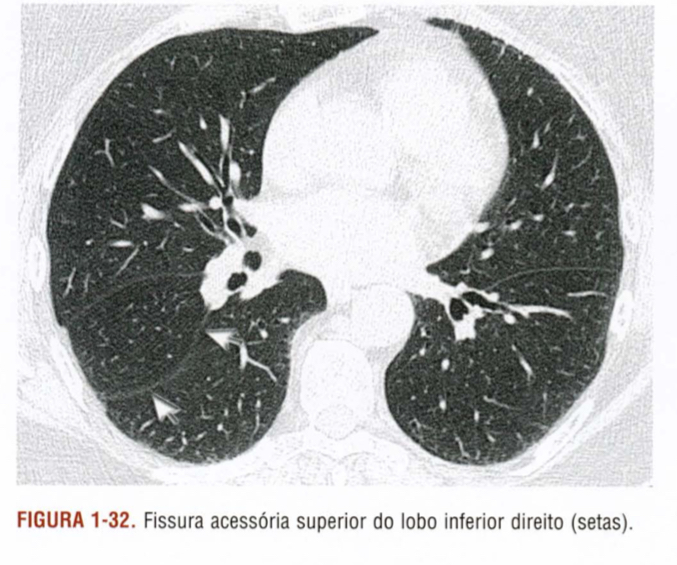

Descreva as fissuras apontadas pelas setas e os lobos pulmonares

Qual a alteração demonstrada pelas setas?